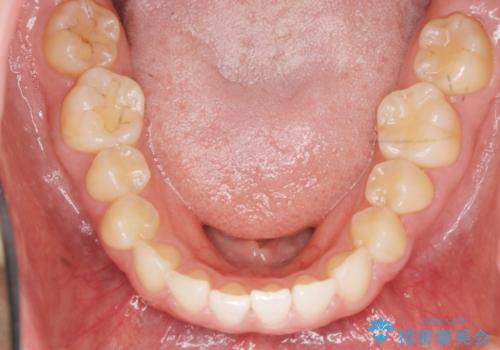

前歯のガタつきをきれいに マウスピース矯正治療

- 「前歯のガタつきをきれいにしたい。」と矯正治療を希望され来院されました。

前歯のガタつきをワイヤー部分矯正、上顎前突の咬合関係を後方移動することで理想的な咬合関係を確立します。

上顎の全体的な後方移動を実現するためにマイクロインプラントを併用したゴムかけを行ったことで理想的な咬合関係を確立することができました。